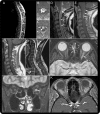

Neuromyelitis optica (NMO) is an inflammatory CNS syndrome distinct from multiple sclerosis (MS) that is associated with serum aquaporin-4 immunoglobulin G antibodies (AQP4-IgG). Prior NMO diagnostic criteria required optic nerve and spinal cord involvement but more restricted or more extensive CNS involvement may occur. The International Panel for NMO Diagnosis (IPND) was convened to develop revised diagnostic criteria using systematic literature reviews and electronic surveys to facilitate consensus. The new nomenclature defines the unifying term NMO spectrum disorders (NMOSD), which is stratified further by serologic testing (NMOSD with or without AQP4-IgG). The core clinical characteristics required for patients with NMOSD with AQP4-IgG include clinical syndromes or MRI findings related to optic nerve, spinal cord, area postrema, other brainstem, diencephalic, or cerebral presentations. More stringent clinical criteria, with additional neuroimaging findings, are required for diagnosis of NMOSD without AQP4-IgG or when serologic testing is unavailable. The IPND also proposed validation strategies and achieved consensus on pediatric NMOSD diagnosis and the concepts of monophasic NMOSD and opticospinal MS.